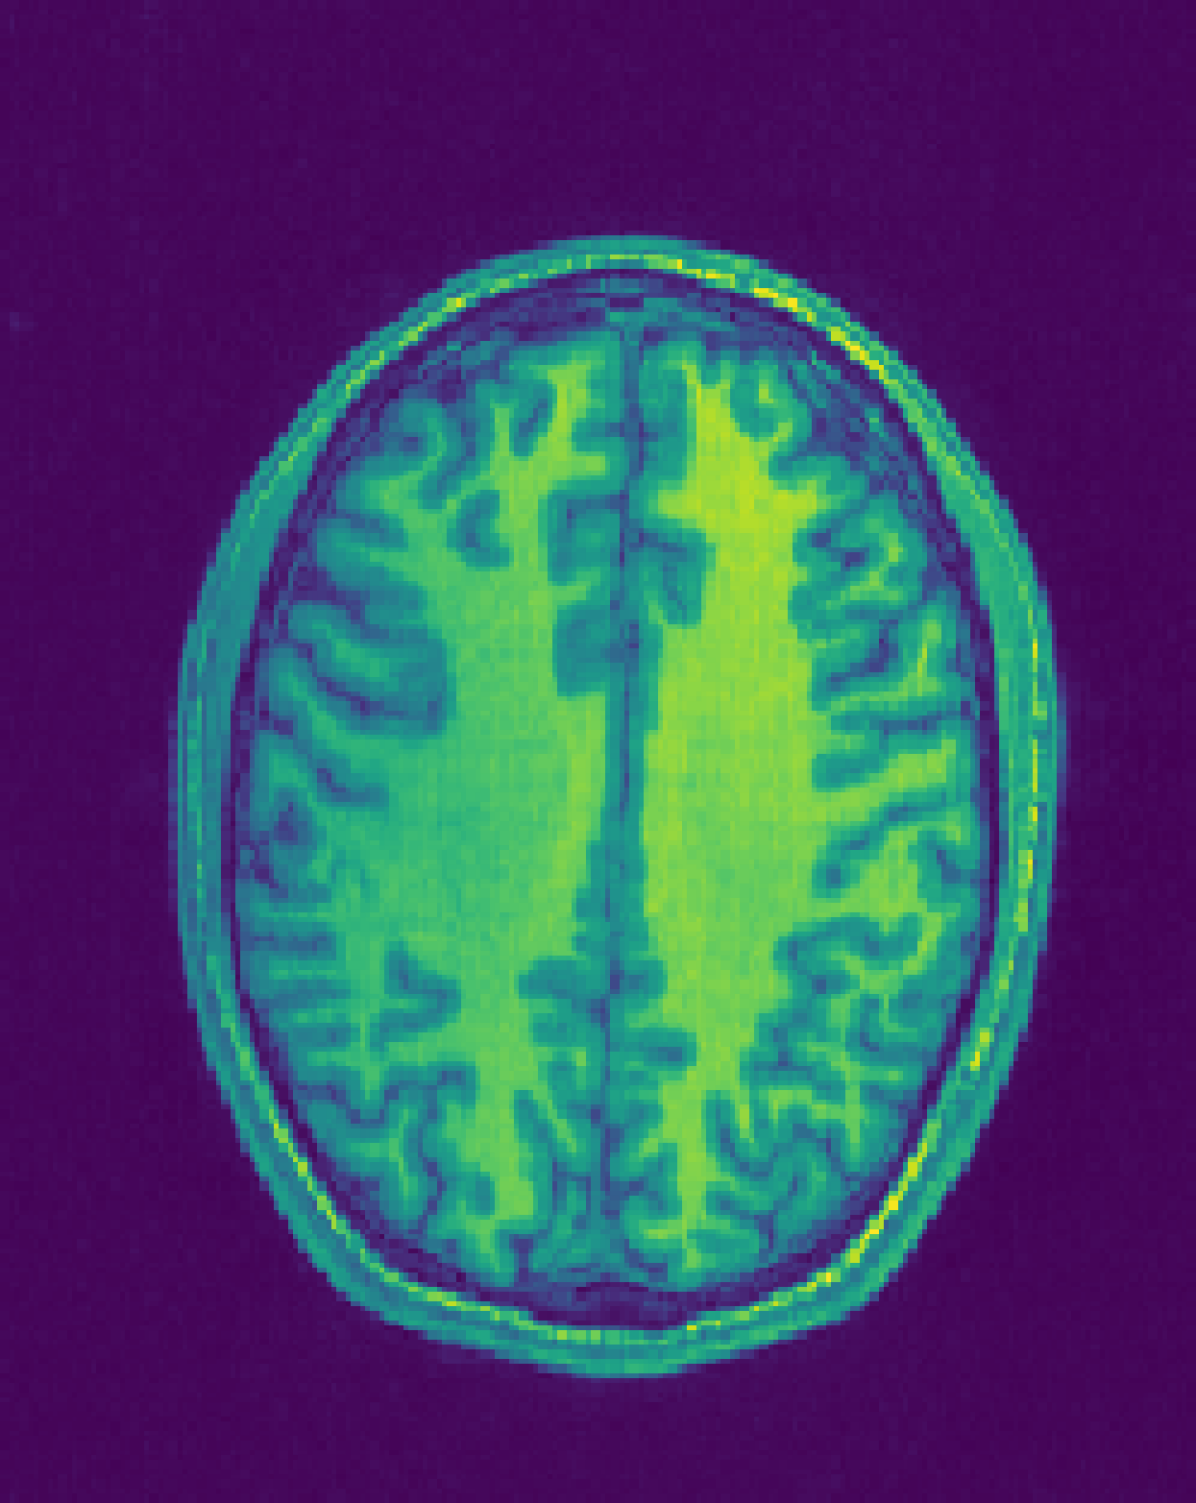

Figure 1: Reconstruction results for R = 3, with (1(a)) the fully sampled image, (b) the zero-filled image, (c) the reconstruction with no bias field estimation, (d) the joint reconstruction with bias field estimation using N4. The first three rows show reconstruction results for an HCP image, its zoomed-in version and the corresponding bias field. The next three rows show results for an in-house measured image. For visualization purposes, MR images are clipped to [0, 1.2] and bias fields, to [0.5, 1.8].

The quantitative improvement is also supported by the visual inspection of the images given in Figure 1. From the HCP image, one can observe that the level of artifacts is reduced with the proposed method. This becomes more evident in the zoomed-in images. The red arrow points to a part of the image where the proposed method can reconstruct the structures faithfully, whereas the baseline method struggles. Aliasing artifacts are globally suppressed better with the joint reconstruction method. Similarly, for the in-house measured image, the grey matter structure that the red arrow points to is not reconstructed in the baseline method, whereas it again appears with the proposed method.